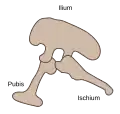

Le pubis (ou os pubis) est la partie antérieure et inférieure de l'os coxal.

Le pubis est relié en haut à l'ilium via l'acétabulum et en arrière à l'ischium en formant la branche ischio-pubienne.

Le pubis est un os qui fusionne avec l'ischium et l'ilium dans l'adolescence, au niveau du cartilage en « Y » au centre de l'acétabulum pour former l'os coxal.

La structure des os du bassin (ischium, ilium et pubis), permet de distinguer au sein de la clade Dinosauria les Saurischia des Ornithischia[7],[8].